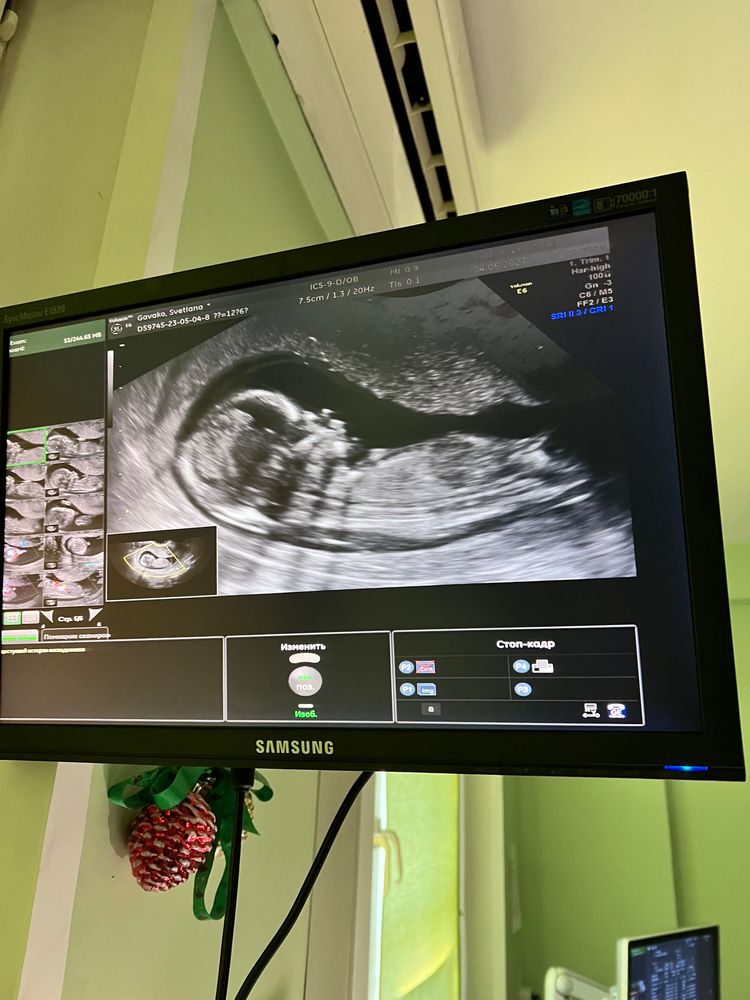

Здравствуйте. Девочки, как думаете кто? Похож ли на мальчика? Могут ли быть ошибки по определению по

В 16 недель ходила на узи для определения пола, сказали мальчик, но на втором скрининге выяснилось, что дочь пуповину между ног зажала)

А у вас что говорят на втором скрининге? Мальчик? Если да, то так оно и есть, на втором уже точно видно